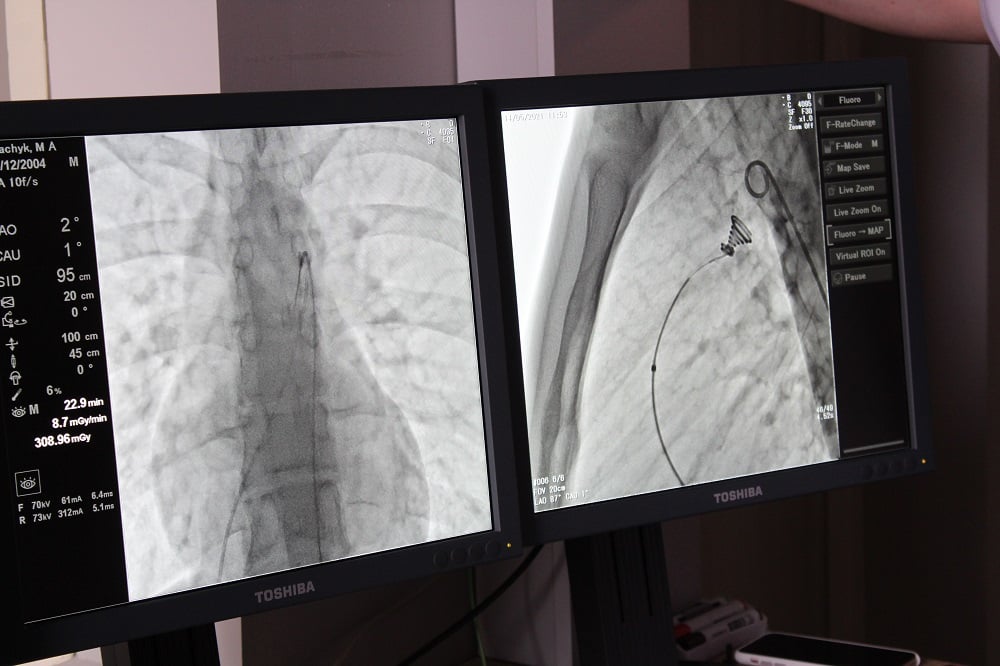

У Ковельському МТМО вперше на Волині провели кардіохірургічну операцію дитині із вродженою вадою серця без розрізу грудної клітини.

У співпраці лікарів Науково-практичного медичного центру дитячої кардіології та кардіохірургії (м. Київ) та відділення інтервенційної радіології Ковельського МТМО успішно виконано операцію із закриття відкритої артеріальної (Боталової) протоки. Це кровоносна судина, яка зазвичай закривається після народження дитини упродовж першого дня життя. Якщо закриття не відбулося, через неї продовжує проходити кров. Такий стан є небезпечним, адже з роками призводить до незворотних змін та серйозних патологій серця, легень, нижніх кінцівок.

Операція пройшла успішно. Вона була складною і проводилась під рентгенівським контролем із застосуванням ангіографа, під місцевим знечуленням (без наркозу). Через прокол у стегновій вені і артерії в незакриту протоку встановлено оклюдер (маленьку пружинку), яка перекрила потрапляння артеріальної крові у венозне русло. Нині юний пацієнт почувається добре і готується до виписки з лікарні, – йдеться на сторінці Ковельського МТМО.